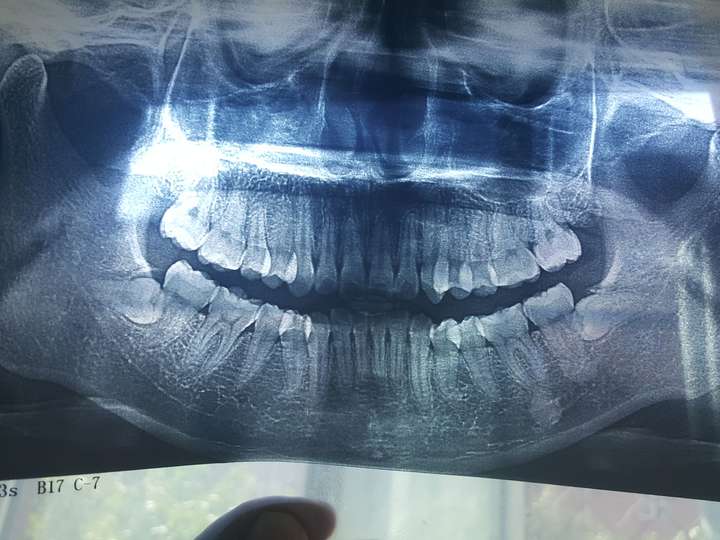

这个长横了的智齿必须拔吗?担心把其他的好牙给挤歪了

图片尺寸600x668